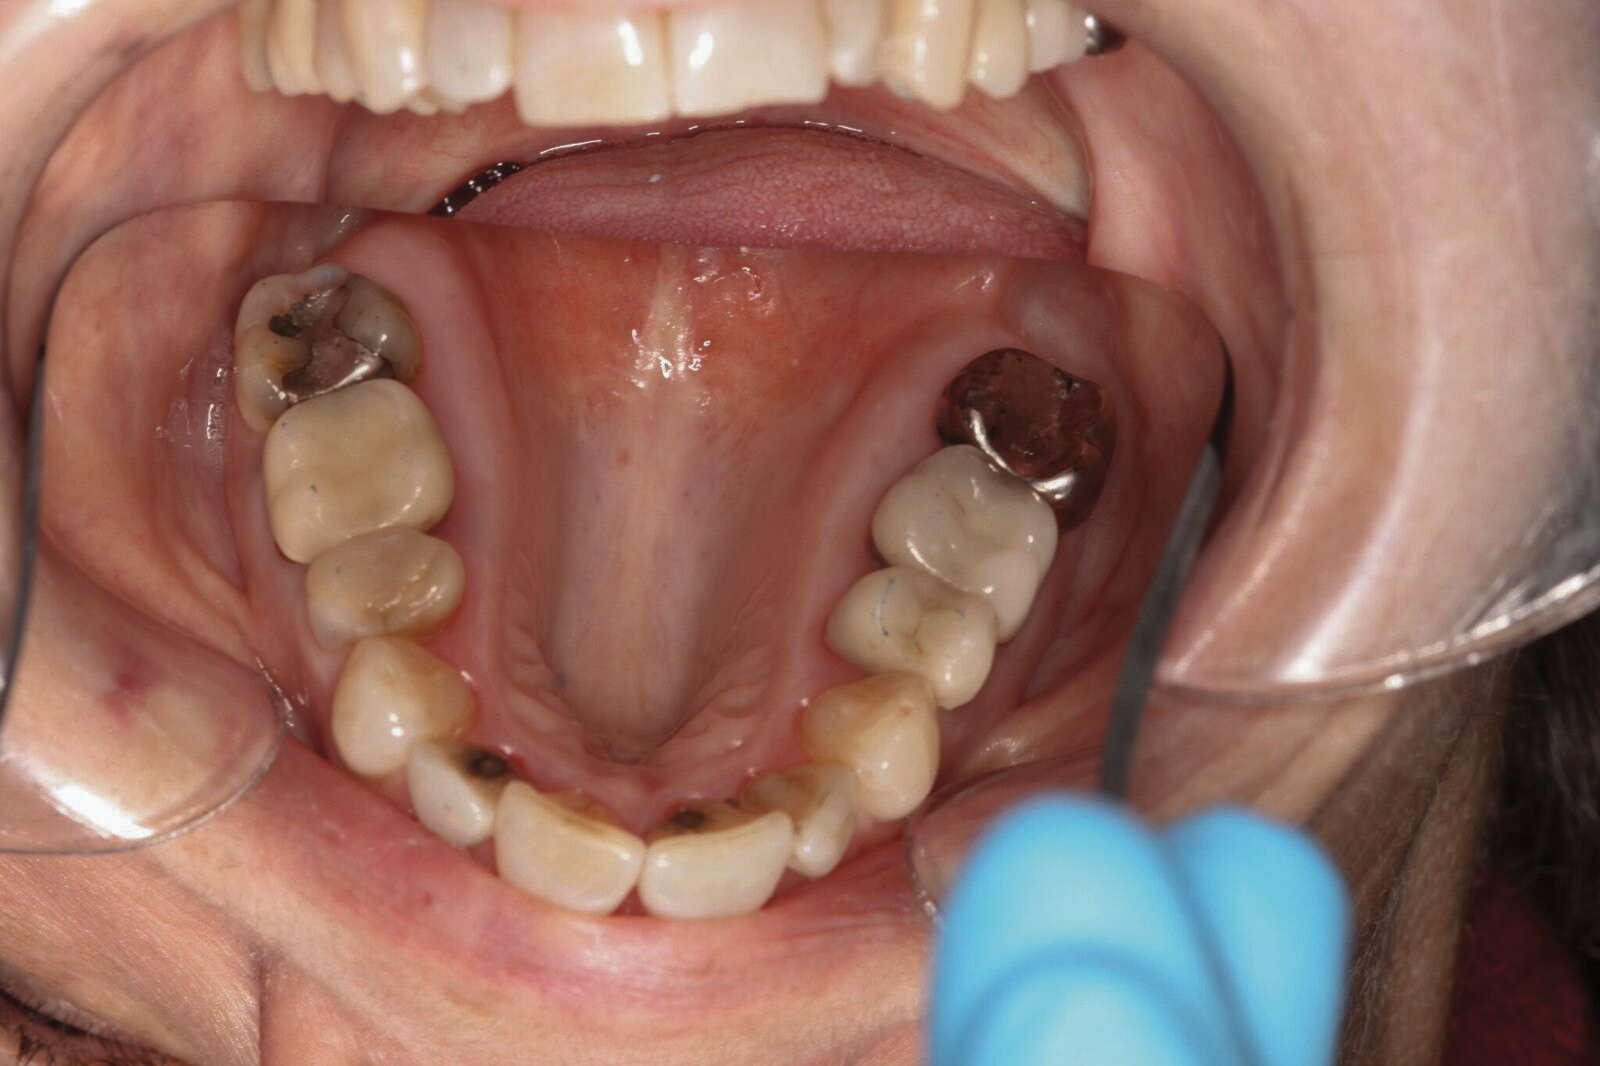

Dental sleep medicine (DSM) is a field in dentistry dedicated to the use and research of oral appliance therapy for the management of snoring and OSA. Oral appliance therapy is a noninvasive alternative to PAP therapy. Oral appliances fabricated by dentists with training in dental sleep medicine are commonly used to reposition the lower jaw forward to increase upper airway patency. Dental professionals have been recognized as being part of the multidisciplinary therapeutic team for the management of OSA because of their prime position of constant examination of the oropharyngeal areas. There are several oropharyngeal features contributing to the development of a narrow upper airway. These features are easily identifiable during a routine dental appointment, such as a large and scalloped tongue (Figure 1), narrow maxilla (Figure 2), small mandible (Figure 3), and retrognathic mandible (Figure 4). Combining clinical history intake, oropharyngeal examination, and the use of validated screening questionnaires, such as the STOP-Bang, dentists can screen for signs and symptoms of OSA and make recommendations for further diagnostic testing.

(2.) Narrow maxillary arch with deep palatal vault.

Figure 2